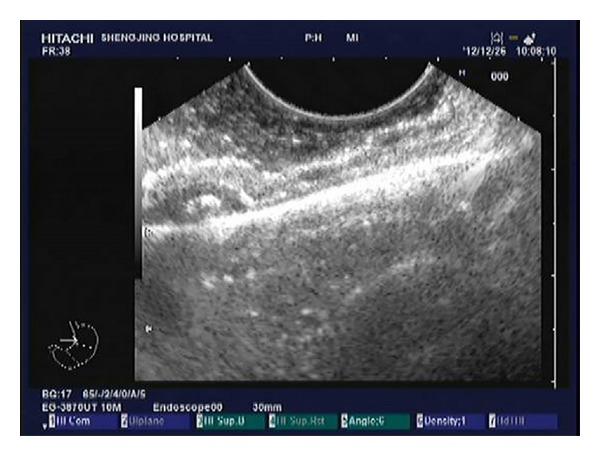

During a standard endoscopy, a transparent cap attached to the endoscopic tip was placed over the lesion to exert sustained maximal aspiration before a rubber band was released. Once a definite ligation was confirmed by EUS, the tumor was enucleated. Four to 6 hemoclips were placed on the folds around the ligation band to reduce the tension of the ligation site.

Hemoclip-reinforced endoscopic band ligation with systematic follow-up using EUS appears to be a simple and effective technique for the resection of small GISTs in the gastric fundus.